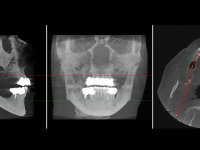

Realizada uma TAC, foi planificada a colocação de 6 implantes no maxilar superior. Foi decidida a colocação de dois implantes na zona dos incisivos centrais, dois implantes na zona dos caninos e dois na zona dos segundos pré-molares. A ausência de estrutura óssea na zona distal do primeiro quadrante implicava a realização de uma regeneração óssea no seio maxilar direito. A cirurgia foi realizada e após a colocação dos implantes foi feita a impressão para confeção de uma prótese provisória metalo-acrílica aparafusada para colocação em carga imediata no dia seguinte. O implante colocado na zona do seio maxilar direito não foi colocado em carga. Passados 6 meses foi realizada a impressão aos 6 implantes com técnica de moldeira aberta e foram confecionados os modelos de trabalho. Numa consulta seguinte foram montados os modelos de trabalho em articulador semi-ajustável utilizando o arco facial e a relação inter-maxilar obtida com a prótese provisória. Foi feita uma muralha de silicone sobre a ponte provisória com o objetivo de orientar o trabalho laboratorial. Realizada a infra estrutura metálica aparafusada esta foi provada em boca e finalmente após colocação de cerâmica o trabalho foi colocado definitivamente. Como passaram vários meses após a realização da primeira TAC foi feita uma segunda para planificar a colocação de implantes no 4º quadrante. Colocaram-se 3 implantes na mesma sessão em que foi feita a extração dos pilares da ponte. Estes implantes foram posteriormente reabilitados com uma ponte metalo-cerâmica aparafusada de três elementos.